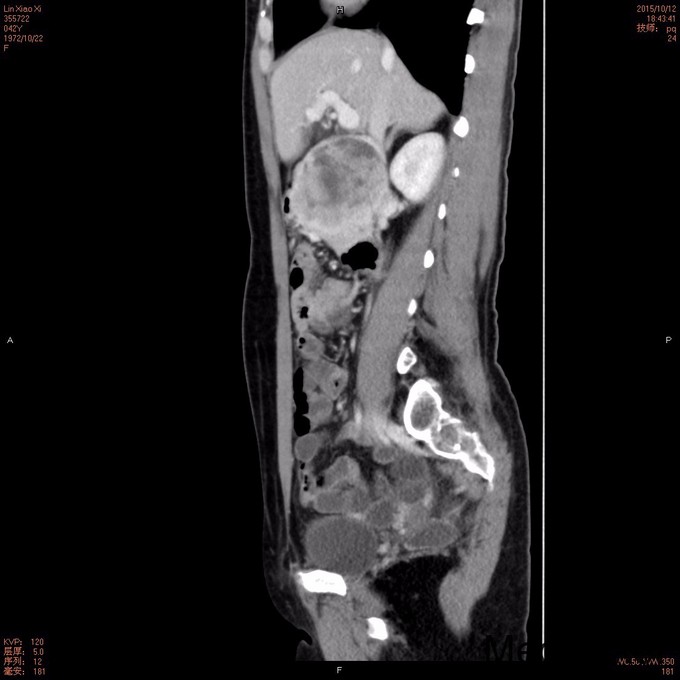

查体: 面色稍苍白,皮肤黏膜及巩膜无黄染,浅表淋巴结未及肿大,无肝掌及蜘蛛痣,无浅表静脉曲张,右上腹肋缘下处可触及一约5cm*5cm包块,界清,质软。 辅查: 电子胃镜:十二指肠降段溃疡未排恶变,病理诊断(十二指肠降段)粘膜组织呈慢炎性 腹部CT平扫+增强:胰头部肿块,考虑囊腺瘤可能性大。

诊断:1.急性上消化道出血,2.胰头占位性病变3.十二指肠降部溃疡 治疗:完善术前检查,在全麻下行“根治性胰十二指肠切除术”,术程顺利,术后病理提示:十二指肠间质瘤,高危险度;出院后休息两周予格列卫口服化疗。